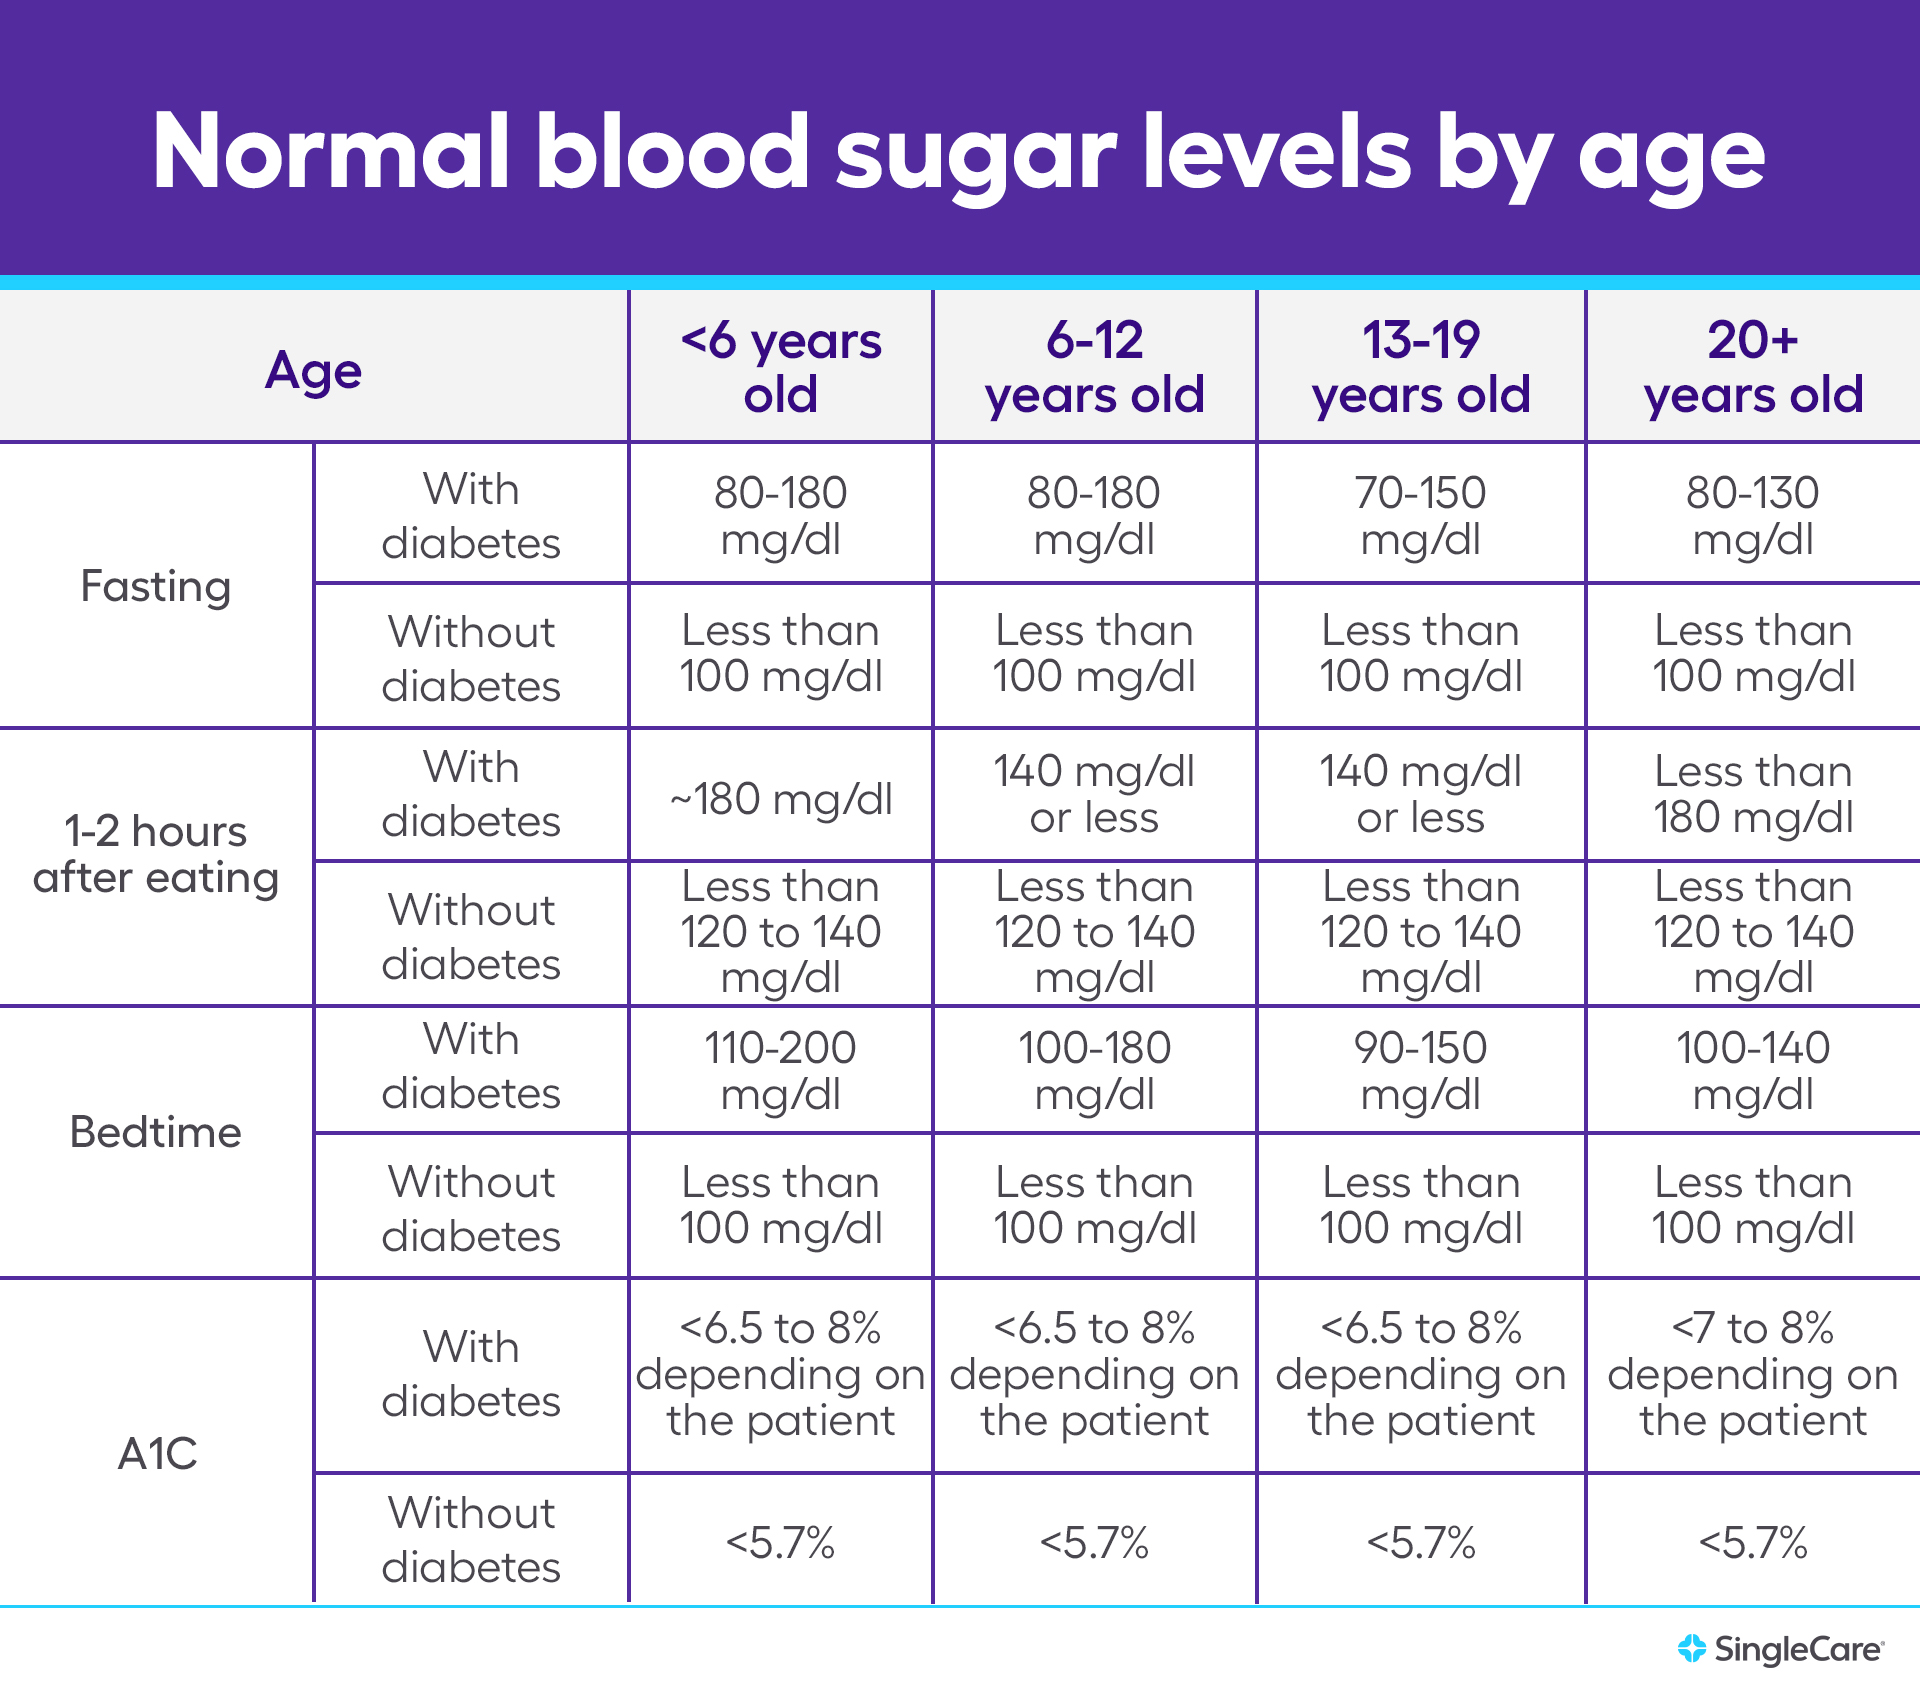

Blood Sugar Chart Understanding A1C Ranges Viasox

25 Printable Blood Sugar Charts Normal High Low TemplateLab

25 Printable Blood Sugar Charts Normal High Low TemplateLab

Normal Glucose Levels Chart